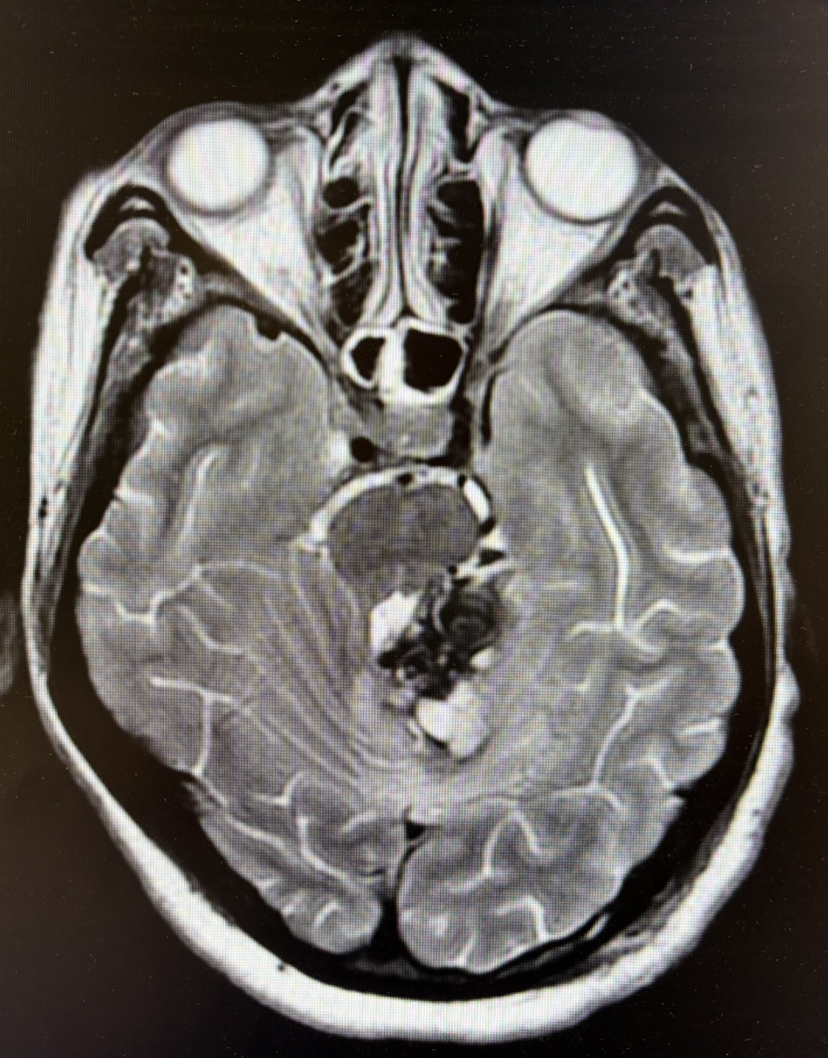

2期术前MRI